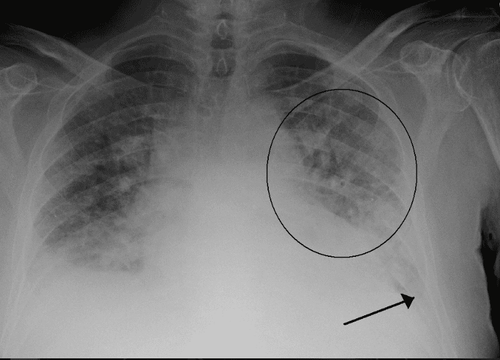

- X-quang tim phổi: Bóng tim to, đám mờ đối xứng từ rốn phổi lan sang hai bên có dạng hình cánh bướm.